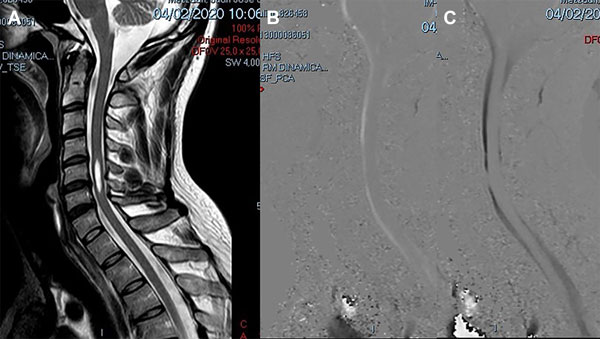

Caso 4: Diagnóstico diferencial

Un varón de 38 años de edad consultó por haber padecido una cérvico braquialgia derecha 30 días antes. En el momento de la consulta sus síntomas habían desaparecido y el examen neurológico fue normal. La RM mostró discopatías cervicales múltiples con una dilatación quística en la médula cervical a nivel C5-C6 que no tomaba el contraste con gadolinio (Figura 6A). Para profundizar el diagnóstico diferencial se realizó una RM en contraste de fase para medir la velocidad del LCR a nivel del canal cervical. La velocidad medida fue de 11 cm/seg (Figura 6B-C). Se hizo el diagnóstico de SM espinal primaria causada por una discopatía cervical a nivel C5-C6. Como el paciente estaba asintomático sólo se indicó control periódico. En su última evaluación, 2 años después, la situación clínica e imagenológica no había cambiado por lo que se mantuvo la misma conducta.

Figura 6: Caso 4. A: RM de columna cervical en plano sagital ponderada en T2 que muestra una cavidad intramedular entre C5 y C6 compatible con siringomielia. B: Estudio de dinámica de LCR que muestra una imagen de magnitud en fase anterógrada con señal hiperintensa el flujo en sístole con disminución del pasaje del LCR en C5-C6. C: Estudio de dinámica de LCR que muestra una imagen de magnitud en fase retrógrada con señal hipointensa el flujo en diástole con la alteración del pasaje de LCR a nivel C5-C6.